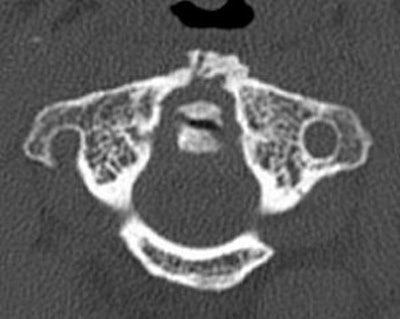

The 0.5-mm slices offer fine bone detail, but pay a price on the soft-tissue images in terms of soft-tissue differentiation. Whereas the thicker (5-mm) slices fail to show the bone detail of the fracture well, but possess greater contrast resolution on the soft-tissue window to differentiate spinal cord from surrounding spinal fluid.

![]() ![]() |